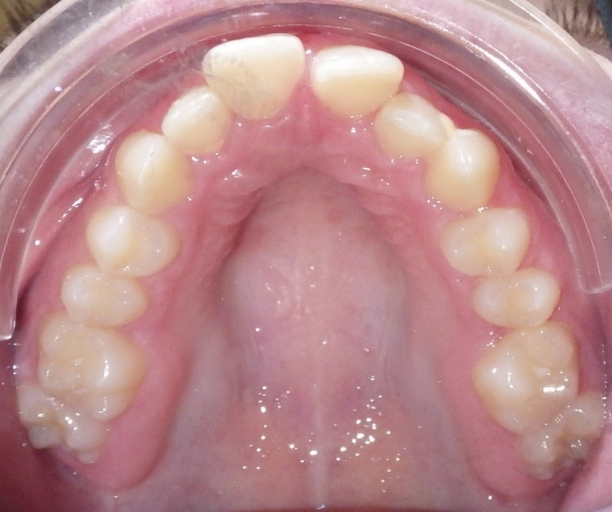

The arch form is also an important factor to evaluate in a Class II pattern. If the upper arch form is narrow, the upper incisors are more protrusive with an increased overjet. (Fig. 5 and 6) The maxilla appears “V” shaped from the occlusal view. (Fig. 7 and 8) The lower arch form is often broader because it is set more posterior in a wider area of the upper arch. If the full upper arch form is not expanded, there will be an excess overjet that remains. Imagine trying to align a round circle into the peak of a triangle. If the full arch is expanded with an expander, the upper and lower arches can coordinate to a normal overjet. (Fig. 4)